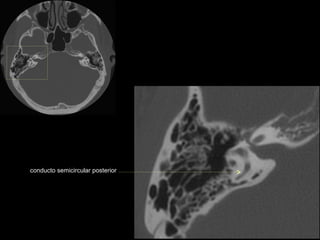

conducto semicircular posterior

CATEDRA DE RADIOLOGIA U.N.L.P.   Hueso temporal normal              Edición 2002

seno maxilar

conducto

carotídeo

auditivo externo

protuberancia

occipital externa

trompa de Eustaquio

conducto auditivo externo

celdillas mastoideas

eminencia piramidal

seno timpánico

receso del n. facial

nervio facial (3era)

estribo (cruras)

nervio facial

ventana oval

martillo

yunque

cóclea

vestíbulo

conducto semicircular externo

articulación yunque/martillo

conducto auditivo interno

antro mastoideo

celdillas retrolaberínticas

conducto semicircular

superior

conducto semicircular superior

cabeza del martillo

procidencia de meninges

tendón tensor del tímpano

conducto carotídeo

espina supra y retrotimpánica

nervio facial (2da)

nervio facial (1era)

cresta falciforme

promontorio

estribo

membrana

timpánica

externo

ventana redonda